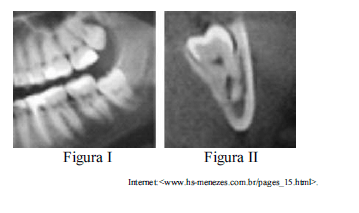

Situação hipotética: A radiografia panorâmica mostrada na figura I apresenta um terceiro molar inferior em posição vertical, com aspecto de curvatura nas raízes abaixo do canal mandibular do nervo alveolar inferior. O laudo da tomografia computadorizada, mostrado na figura II, aponta o siso 38 em infraversão e o canal mandibular posicionado entre as raízes mesial e distal desse mesmo dente, com o envolvimento de seu trajeto. Assertiva: Nesse caso, a remoção do siso deve ser feita mediante a separação das raízes para prevenir uma parestesia permanente do nervo alveolar inferior e metade do lábio inferior do mesmo lado do dente.